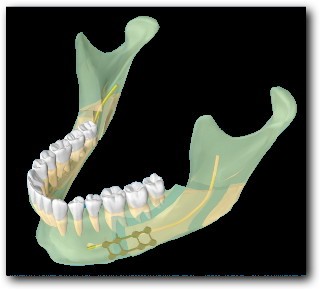

La technique classique est une ostéotomie Basse et longue, le long du nerf alvéolaire inférieur. C’est l’ostéotomie d’Epker, modifiée par Obwegeser. Elle présente pour inconvénient principal d’entrainer une perte de la sensibilité de la lèvre. Par ailleurs, parfois le bord osseux est irrégulier, ce qui peut se voir, ou être inconfortable dans certaines positions.

Les deux premières (Obwegeser et Epker) se ressemblent. La technique d’Eplker est une évolution de la première. Elles présentent toutes les deux l’inconvénient de se réaliser le long du nerf alvéolaire inférieur, et d’entrainer une hypoesthésie partielle dans certains cas (7 à 67% des cas selon les séries).

La technique de l’ostéotomie Haute présente l’avantage de se situer au dessus du nerf. Les pertes de sensibilité sont donc moins fréquentes (0,4 à 0,5% des cas selon les séries).

Ostéotomies Basses

Les ostéotomies basses peuvent être intéressantes dans certaines asymétries horizontales, mais augmentent le risque de troubles de la sensibilité de la lèvre en post-opératoire. Par ailleurs, elles ne permettent pas d’abaisser l’angle de la mandibule dans les asymétries verticales, et une décalage osseux du bord inférieur peut être gênant.

Ostéotomies Hautes

L’ostéotomie Haute de la mandibule est plus courte et diminue donc le risque d’atteinte du nerf alvéolaire inférieur (qui détermine la sensibilité de la lèvre inférieure). Elle permet également de remonter ou d’abaisser l’angle de la mandibule, sans que le décalage osseux ne puisse être visible ou palpable. Il s’agit d’une technique mini-invasive dont les suites sont simples.

Technique Chirurgicale

La technique chirurgicale a été décrite décrite par Perthes Schliessmann en 1932. Il s’agit de l’ostéotomie mandibulaire Haute, ou courte, ou sus-spigienne. La plus grande difficulté est technique, puisque l’ostéosynthèse est très haute. Le tournevis contre-angle de Fritzemeier permet de limiter la taille de l’incision. Cet instrument permet de réaliser une chirurgie mini-invasive.